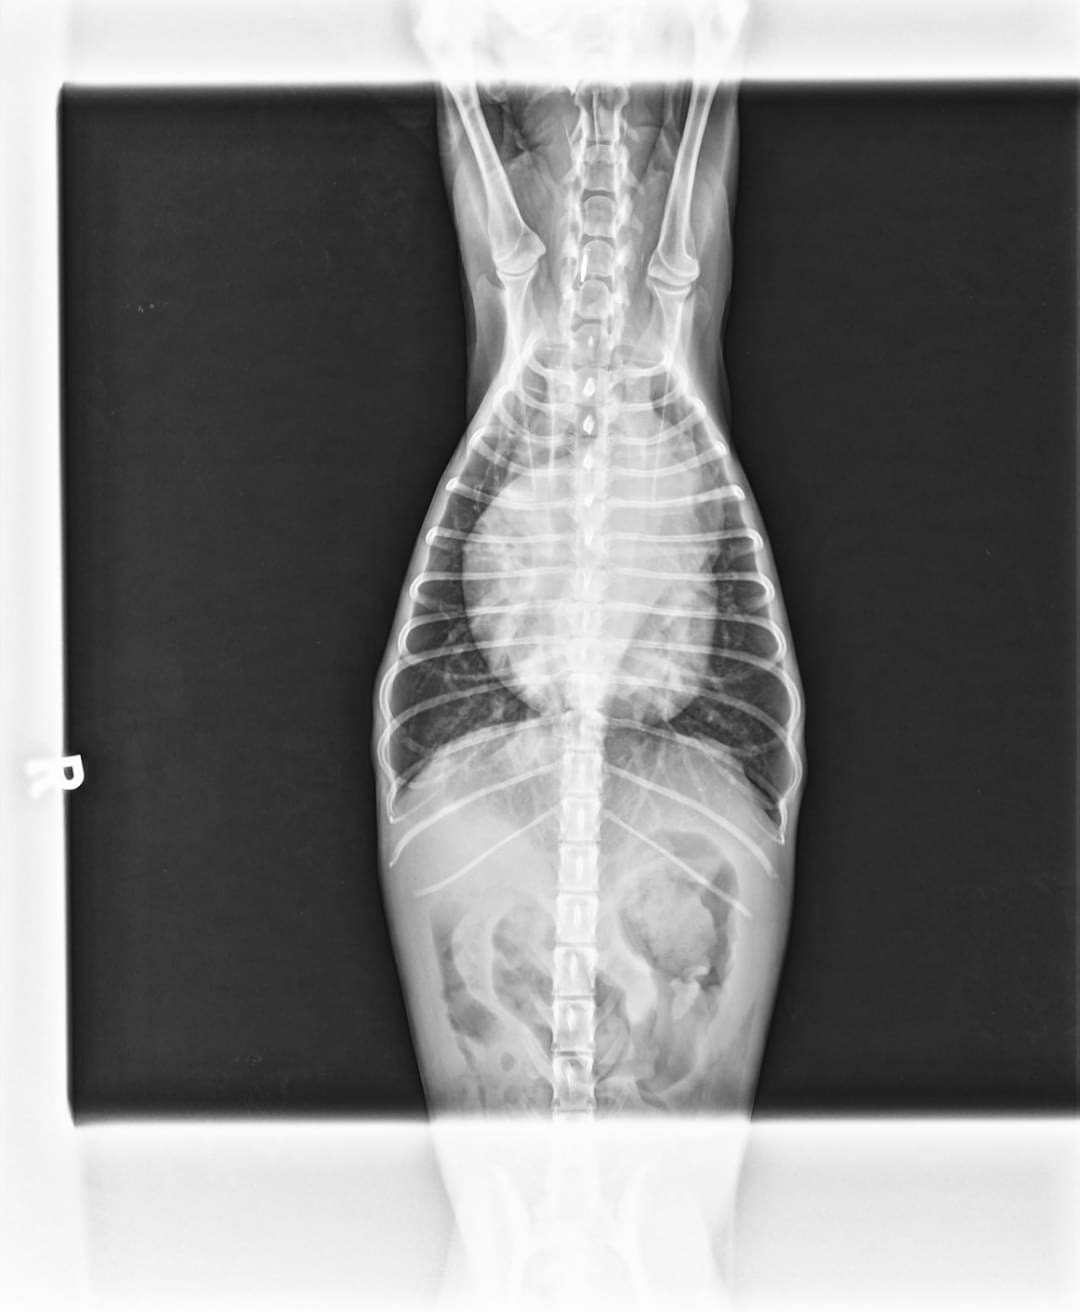

血液學檢查排除心絲蟲感染,並無明顯白血球上升跡象,X光影像學檢查下,可明顯發現動物心臟整體變大,主肺動脈幹明顯膨大,腹腔的輪廓度下降。